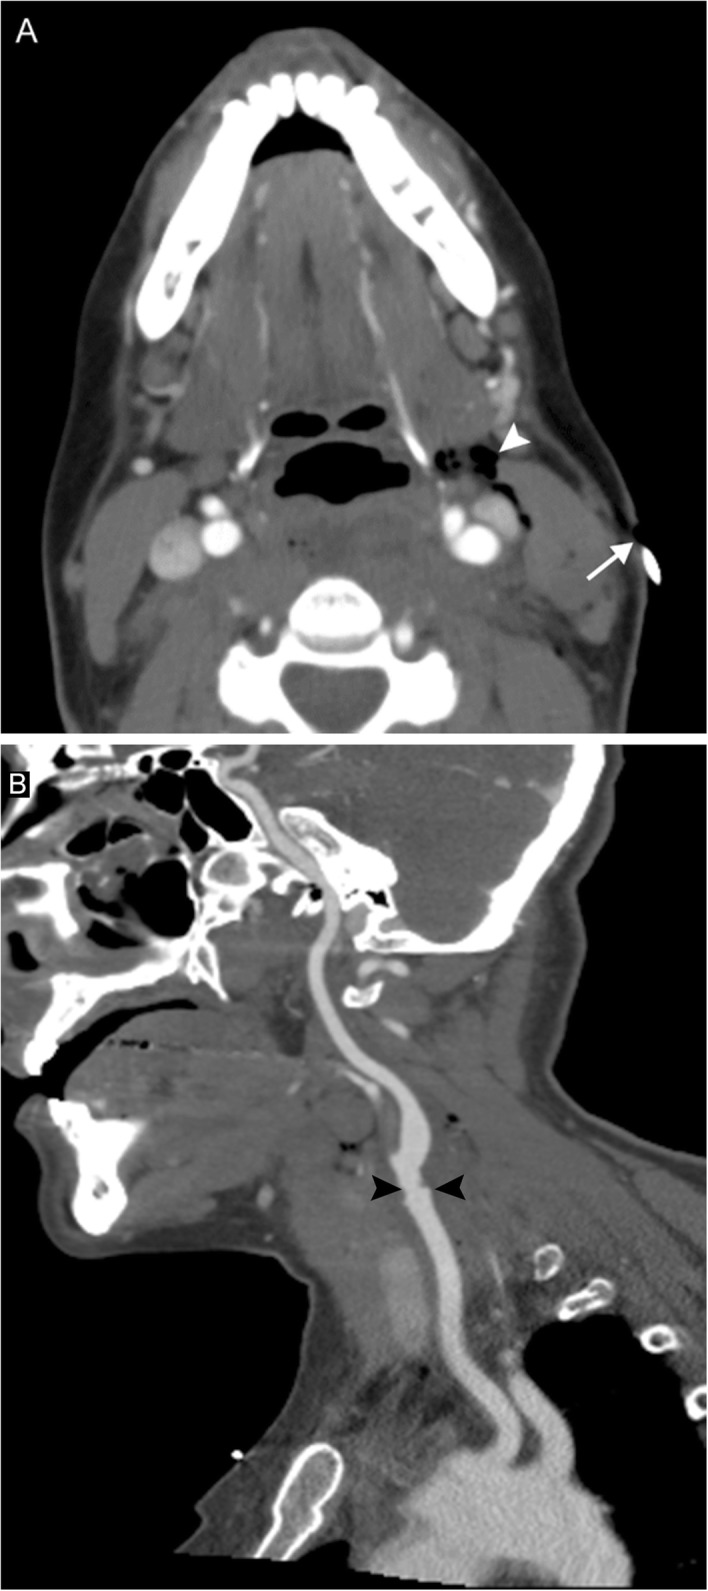

Fig. 7.

Oropharyngeal squamous cell carcinoma. A 40-year-old man presenting with tender neck mass, dysphagia to solid food, odynophagia, and voice changes. Axial (a) and sagittal (b) contrast-enhanced CT images reveal an enhancing mass at the left oropharynx (arrows) and extensive left-sided lymphadenopathy, including a large level II nodal conglomerate with central areas of necrosis (arrowheads). Biopsy revealed this to be human papilloma virus (HPV)-mediated squamous cell carcinoma. Voice change was attributed to encroachment upon the carotid space resulting in vagal nerve irritation.